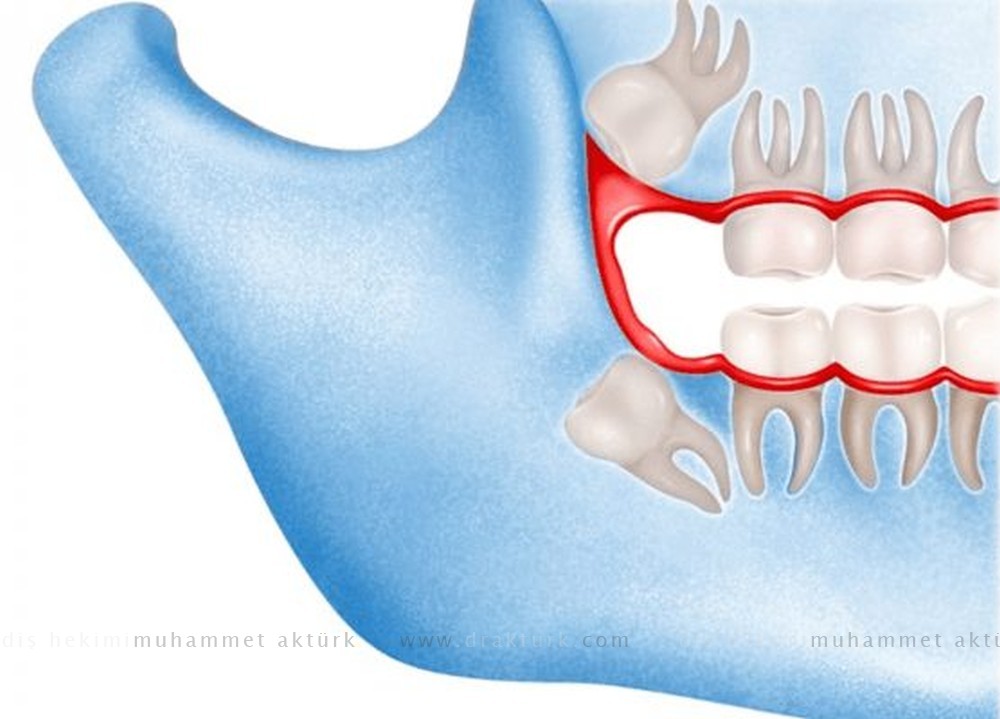

مشاكل مع ضروس العقل المطمورة

من المرجح أن تحتاج إلى خلع ضرس العقل المطمور إذا نتج عنه مشاكل مثل:

- الألم

- حجز الطعام والمخلفات خلف ضرس العقل

- عدوى أو مرض باللثة (مرض دواعم اللثة)

- تسوس الأسنان في أحد ضروس العقل المنبثقة جزئيًا

- تلف بسن قريبة أو العظم المحيطة بها

- نمو كيس ممتلئ بالسوائل (كيسة) في المنطقة المحيطة بضرس العقل

- حدوث مضاعفات من علاجات تقويم الأسنان لتصحيح استقامة أسنان أخرى